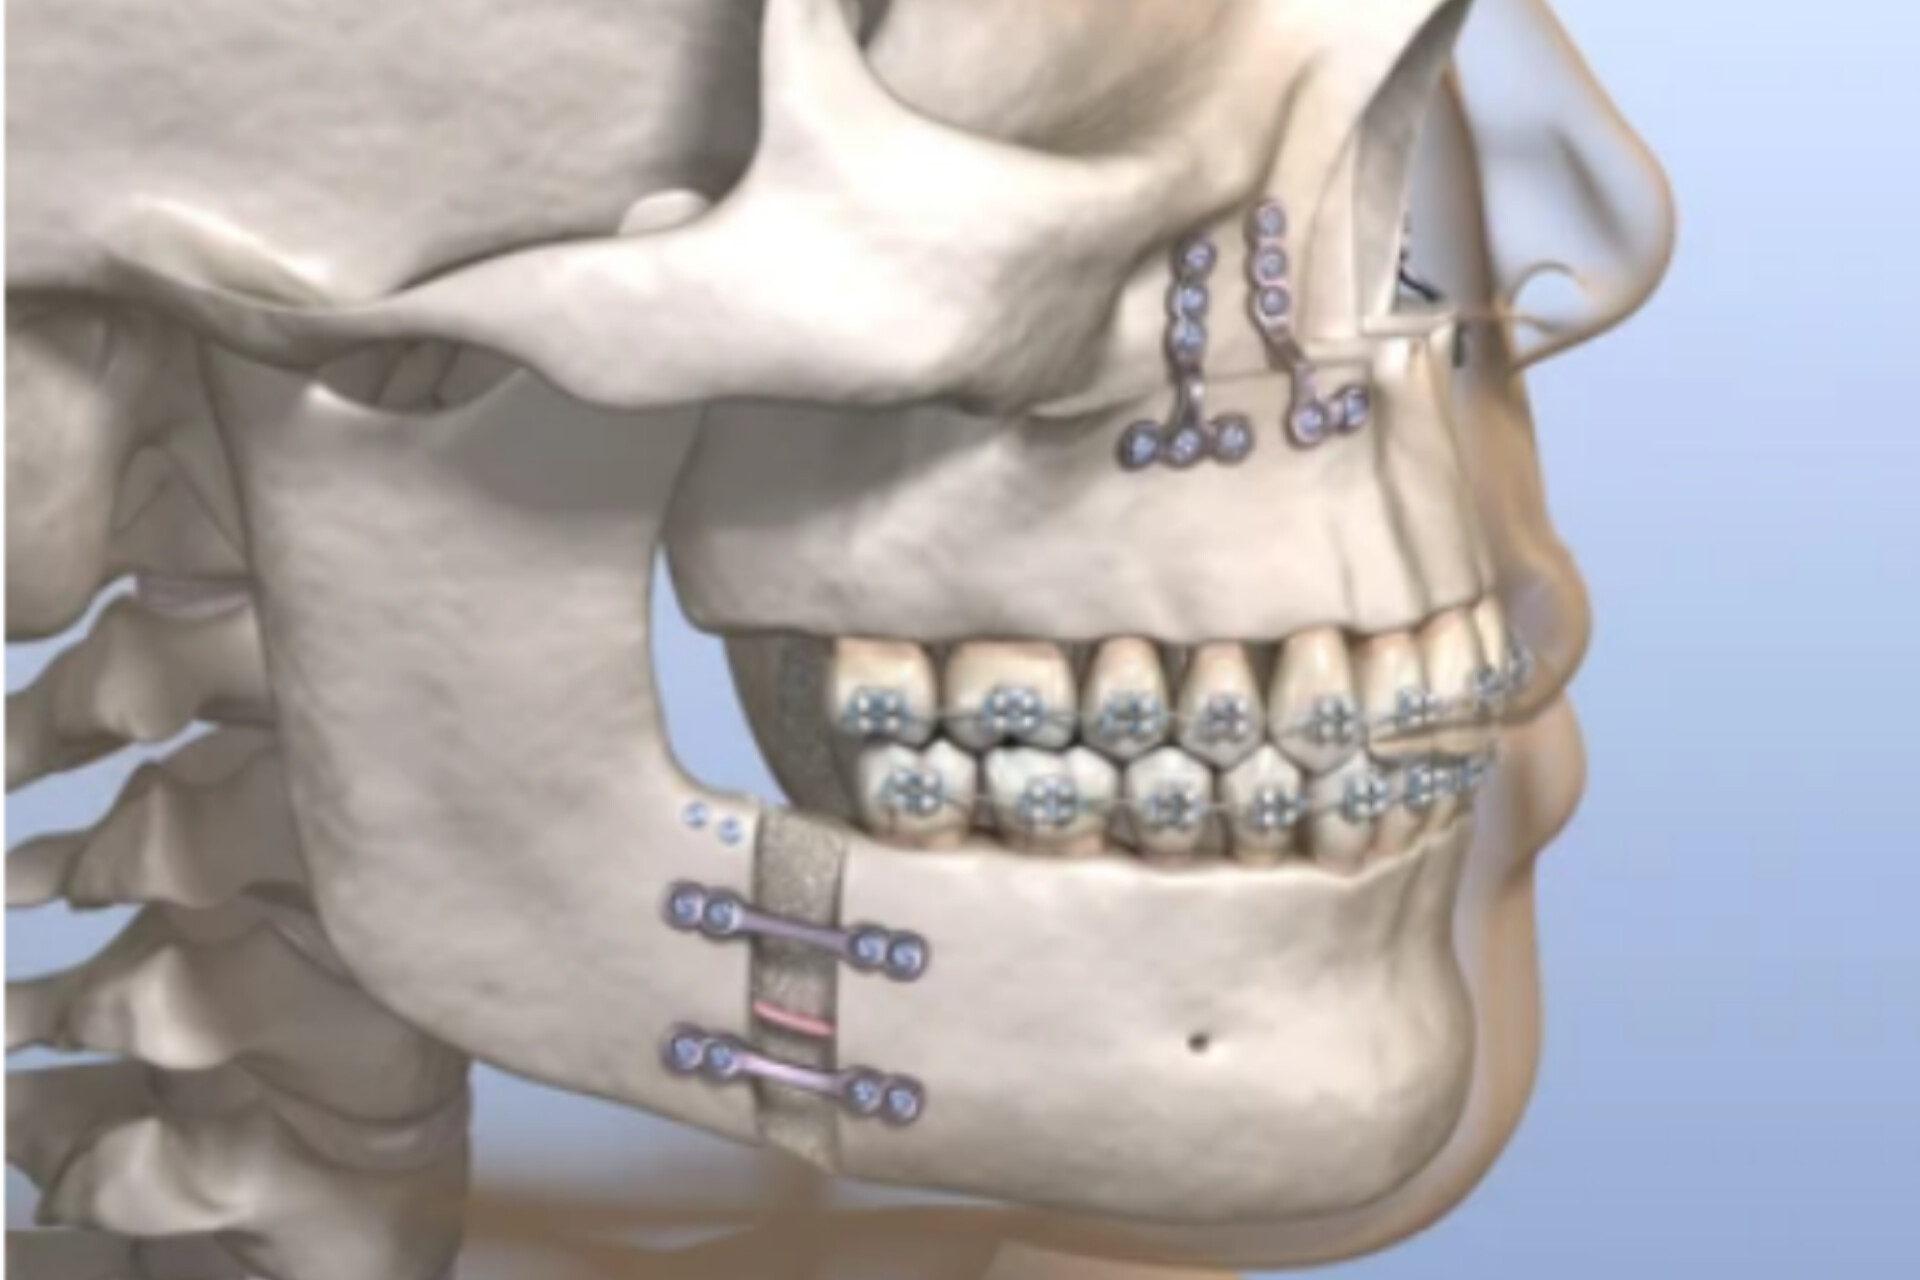

ORTHOGNATHIC SURGERY

Orthognathic Surgery refers to “straightening of the jaw(s) using surgery” [ortho – straight, gnathic – jaw(s)]. Whereas orthodontic treatment corrects the position of the teeth, Orthognathic surgery positions the bones of the jaws (maxilla/mandible). One or both jaws may be surgically repositioned during the one operation. This involves making cuts (osteotomies) in the bones and moving the cut segments into their predetermined position under a general anesthesia. The surgery is normally preceded by a period of orthodontic treatment so that post-operatively both the teeth and the bones will be in their correct position. Finally, a short period of orthodontic treatment is then usually required to complete the alignment of the teeth.